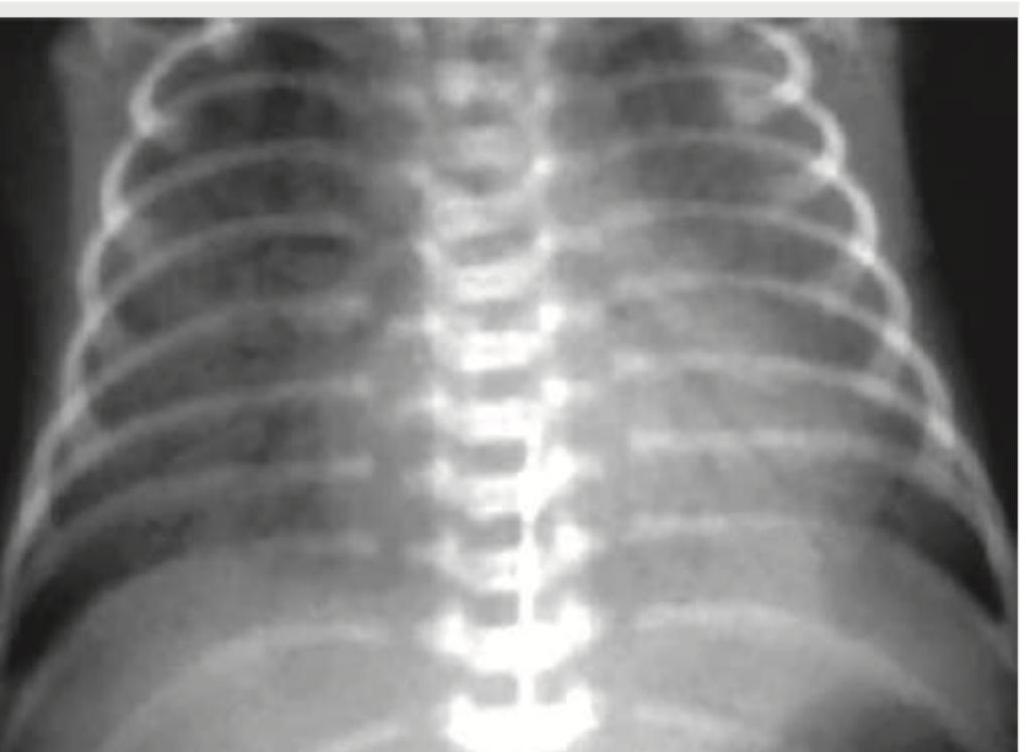

A 1-day-old neonate, born via home delivery, is brought with respiratory distress. The given CXR shows:

Explanation: ***Congenital diaphragmatic hernia*** - The chest X-ray likely shows bowel loops within the chest cavity, mediastinal shift, and an absent or poorly defined diaphragmatic outline, which are classic signs of a **congenital diaphragmatic hernia**. - A 1-day-old neonate with respiratory distress and these radiographic findings strongly suggests this diagnosis, as it results from incomplete **closure of the diaphragm** enabling abdominal organs to herniate into the thorax. *Hyaline membrane disease* - Characterized by **diffuse reticulogranular infiltrates** and **air bronchograms** due to surfactant deficiency. - Does not typically present with bowel loops in the chest or mediastinal shift. *Meconium aspiration syndrome* - CXR typically reveals **patchy infiltrates**, **hyperinflation**, and sometimes **pneumothorax** or **pleural effusions**. - There is no evidence of bowel in the chest or mediastinal shift characteristic of diaphragmatic hernia. *Transient Tachypnea of newborn* - CXR findings usually include **prominent perihilar streaking**, **fluid in the fissures**, and **hyperinflation**. - This condition resolves within 24-48 hours and doesn't involve herniated abdominal organs in the chest space.